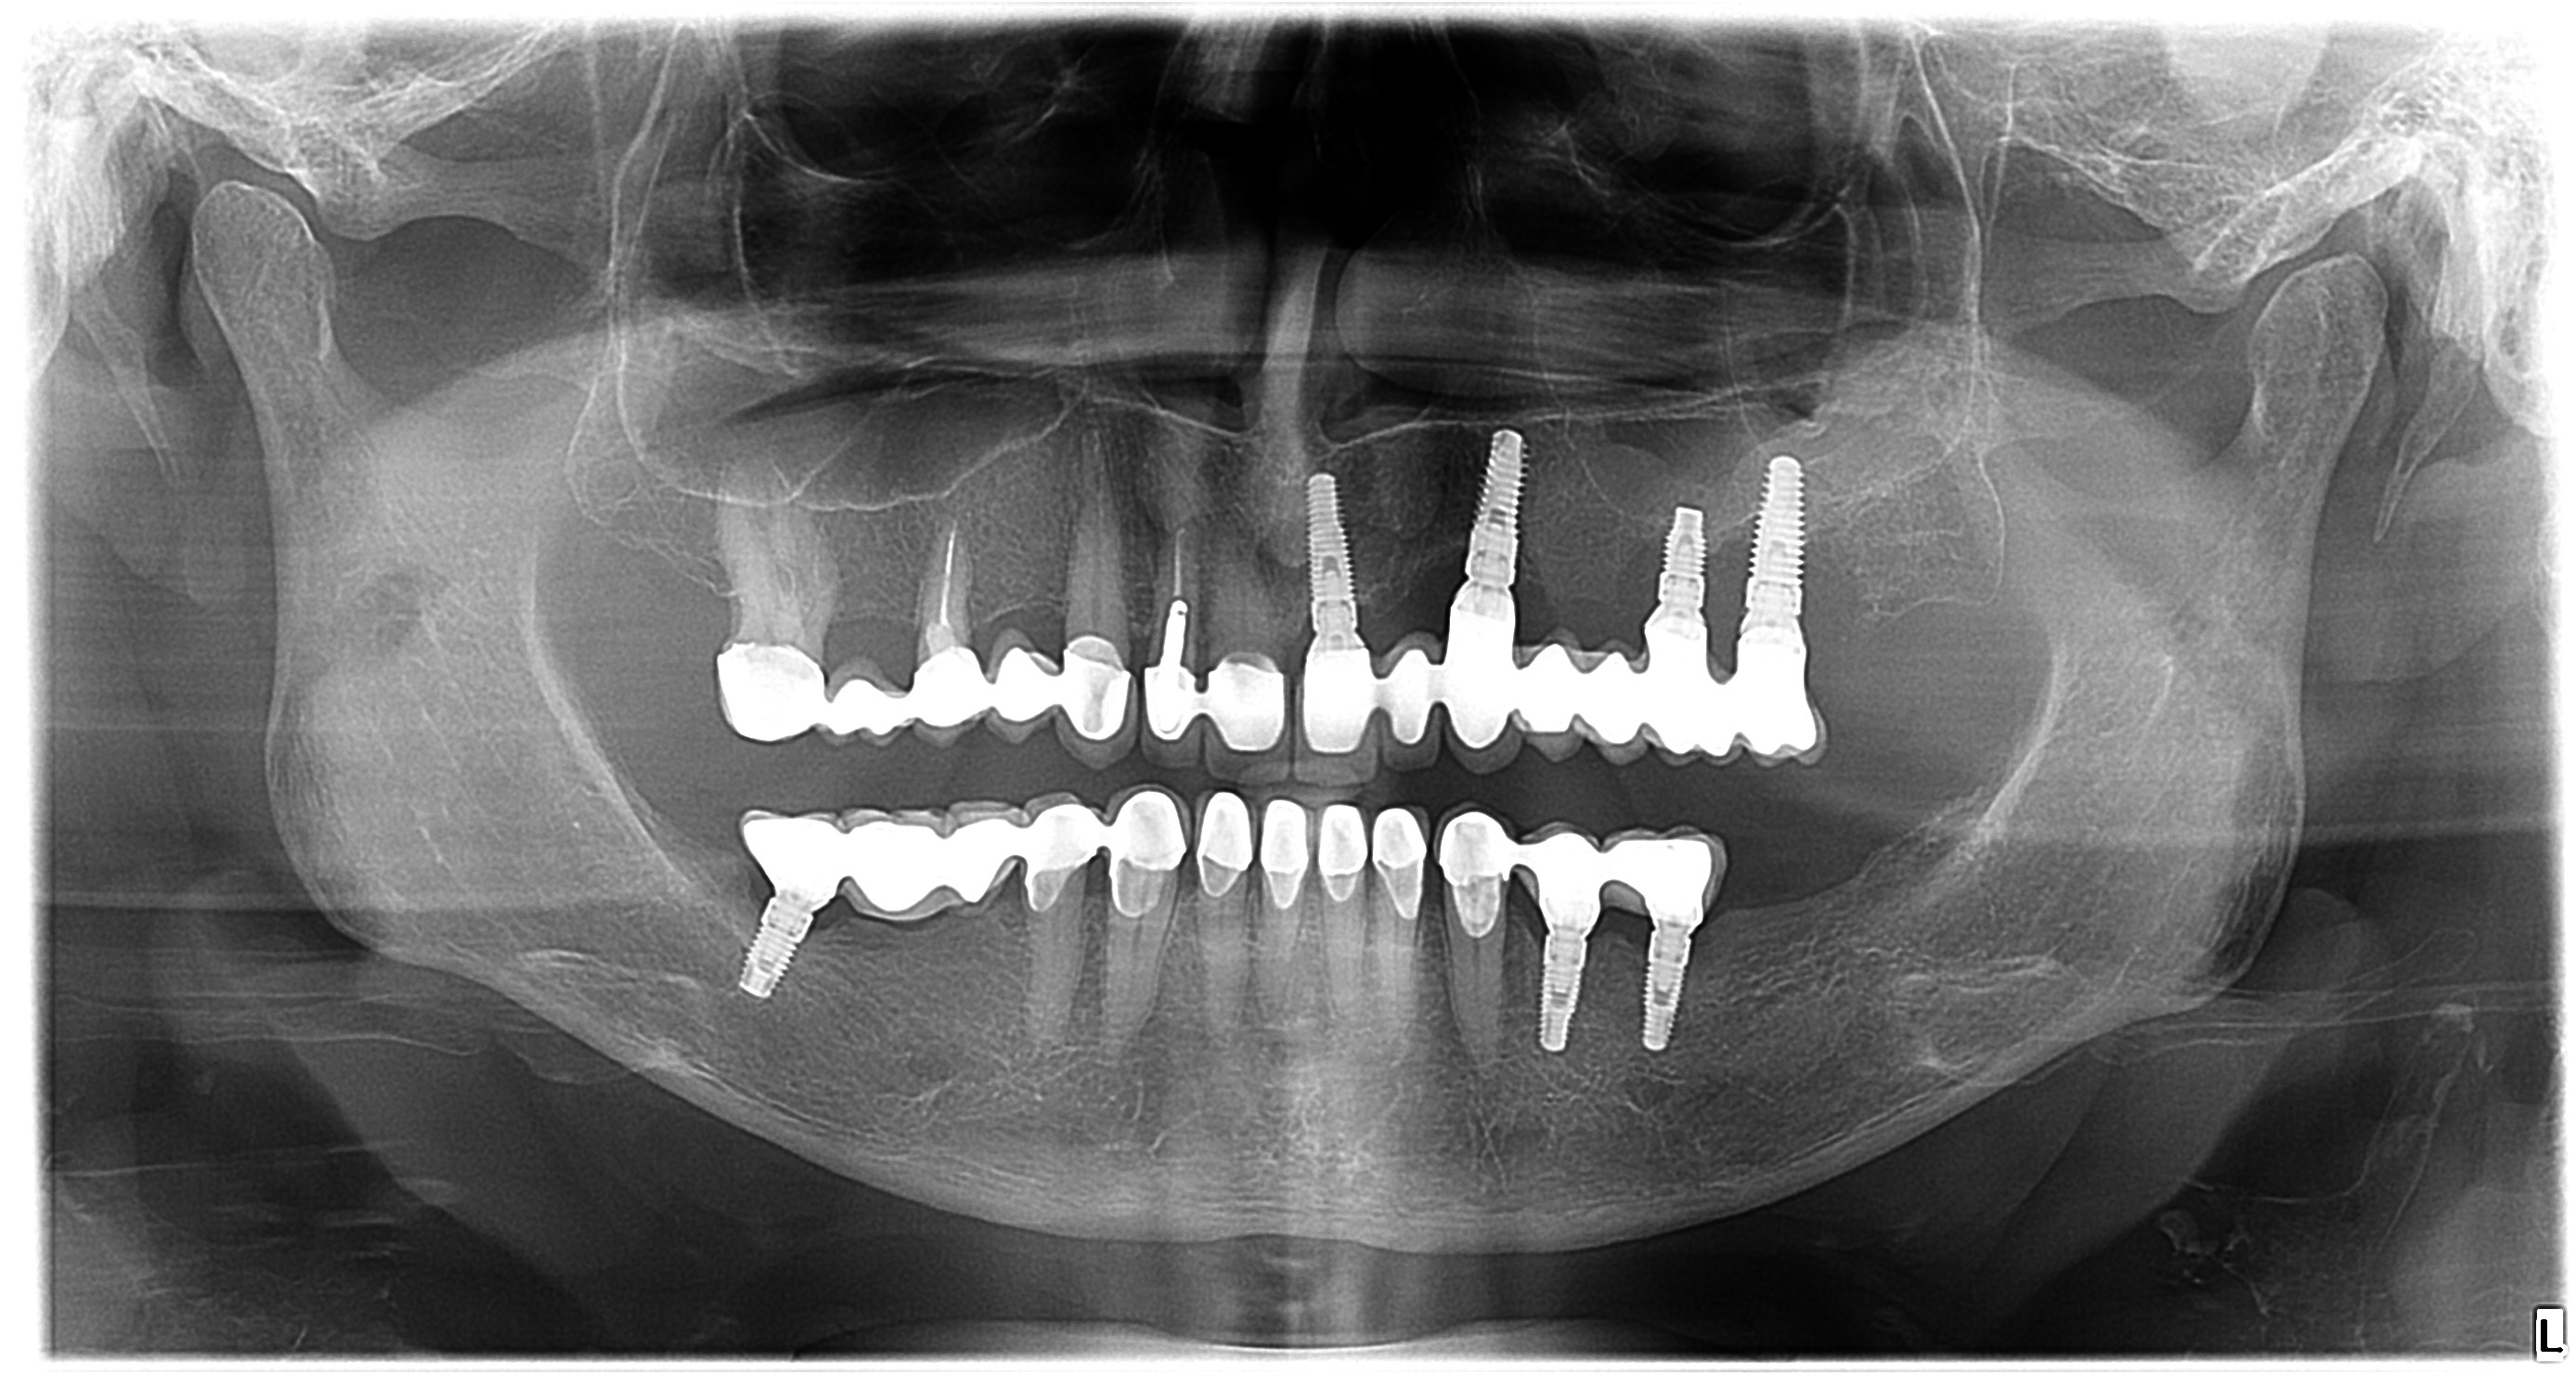

Digitalna tehnologija je unaprijedila medicinske dijagnostičke postupke, a to se posebno odnosi na stomatološku praksu. Kada je riječ o dentalnom rendgenu, digitalni ortopan predstavlja značajan napredak u odnosu na tradicionalne rendgenske snimke. Evo nekoliko ključnih prednosti digitalnog ortopana u odnosu na klasične snimke:

Digitalni ortopan omogućuje visoku razlučivost slike, što znači da stomatolozi mogu dobiti vrlo detaljan prikaz svih zubnih struktura i okolnih tkiva. To je od iznimne važnosti jer precizna dijagnostika pomaže u otkrivanju čak i najmanjih problema s oralnim zdravljem.

Digitalni ortopan dolazi s dodatnim funkcijama obrade slike, kao što su povećavanje i mjerenje. To omogućuje stomatolozima da pažljivo analiziraju i procjenjuju podatke, što može dovesti do preciznije dijagnostike i planiranja liječenja.

Digitalni ortopan predstavlja značajan napredak u stomatološkoj dijagnostici u odnosu na tradicionalne rendgenske snimke. Njegovo korištenje pridonosi unaprjeđenju oralnog zdravlja pacijenata i omogućuje bolje planiranje i provođenje stomatoloških tretmana.